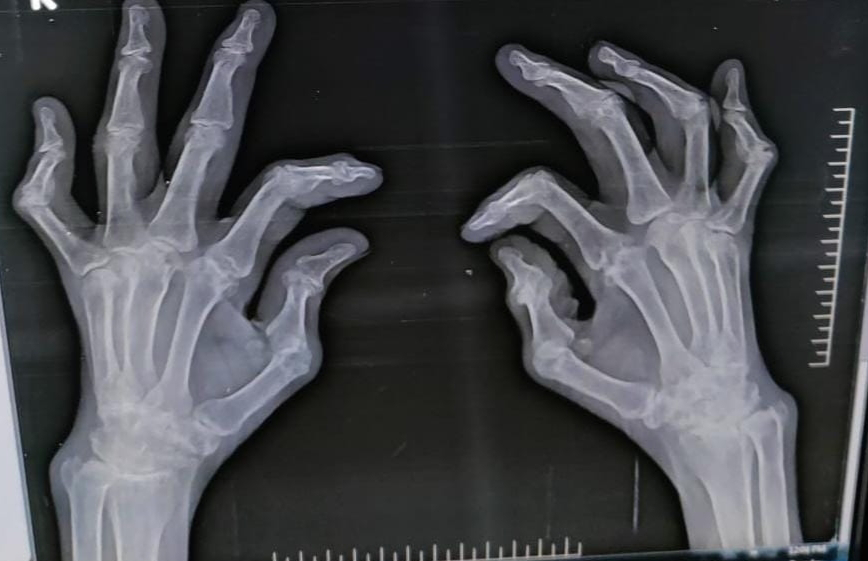

50y/F with multiple joint pains

c/o multiple joint pains since 1 year

Patient was apparently asymptomatic 1 year back then she developed pain over the DIP,PIP,MCP, elbow joint,knee joint,ankle joint ,MTP joint

Tab.Methotrexate 7.5 mg on Sundays (weekly once)

Tab.folic acid 5mg alternate days po/od

Tab hcq 400mg po/od